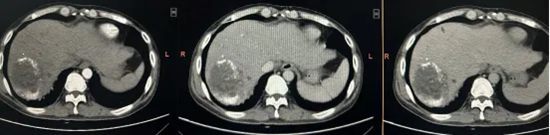

然而,现实是残酷的:肿瘤体积依然顽固,未见明显缩小。更棘手的是,由于反复治疗,肿瘤位置不仅深在,还紧紧毗邻下腔静脉、肝门部大血管与胆管。腹腔内粘连严重,解剖结构早已紊乱得像一团乱麻。面对如此高的手术风险,最终未能实施进一步手术治疗。

为给患者争取根治机会,陈艳军主任团队反复判读影像资料,详细评估病情,周密制定方案,最终决定实施腹腔镜右半肝切除术。

肿瘤体积巨大且紧邻下腔静脉,手术难度极大,稍有不慎将会出现难以控制的大出血,危及患者生命。

最终,手术历时约4小时,陈艳军主任团队冷静应对,精准解剖肝门Glisson系统,依次安全处理肝动脉、门静脉、肝静脉及肝短静脉,沿肝中静脉精准离断肝实质,在彻底切除肿瘤的同时,最大限度保留正常肝脏组织,实现了微创、精准、低出血、保功能的理想效果。